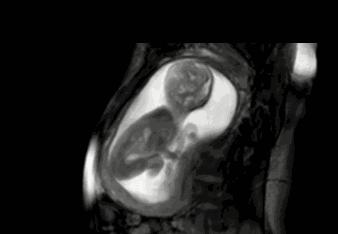

其实小家伙很小的时候就已经开始“闹腾”了:妥妥的一个运动健将!

小碎步向前缩,撅着小屁股用力一蹬,身体向后滑去——“母胎版蛙泳”动作很标准嘛!

不行,刚才的动作不够标准,再来一次!

不过,力气好像还是太小了,算了,休息休息再说~